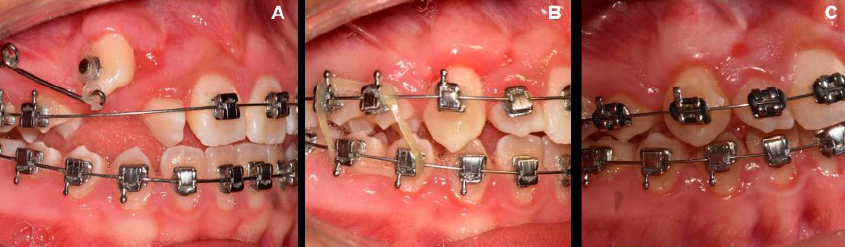

El procedimiento quirúrgico se realizó mediante la técnica de colgajo de reposición apical previamente descrita en el caso 1, tanto para el diente 13 como para el diente 23; con la única diferencia de que en el diente 13 se eliminó una cortical ósea previo al retiro del folículo de tejido conectivo (Figura 2. A-B). La tracción del diente 23 se activó a las dos semanas posquirúrgicas a partir de una ligadura metálica cerrada TD fijada desde el botón ortodóncico (Borgatta®), adherido por sistema adhesivo 3M®, en dirección al diente 21 para guiar la erupción; la tracción se llevó a cabo de manera intermitente durante seis meses.

Figura 2 Técnicas de cirugía plástica periodontal para la exposición de los dientes 13 y 23. Caso 2. A. Diseño de un colgajo de espesor parcial que se reposicionará apicalmente sobre ambos dientes. B. Colocación de botones de ortodoncia y reposición apical de los colgajos a partir de puntos simples y sutura de ácido poliglicólico 6-0.

Seis meses posteriores a la cirugía, se observó que el tejido queratinizado adyacente al botón ortodóncico del diente 13 estaba cubriéndolo y no facilitaría la colocación del bracket para la futura tracción dentaria, por lo que se decidió realizar una segunda cirugía con colgajo de reposición lateral, luego de retirar el botón de ortodoncia (Figura 3. A-D).

Figura 3 Técnica de cirugía plástica periodontal para exposición de diente 13, 6 meses posteriores a la cirugía. Caso 2. A. Presencia de tejido queratinizado lateral al diente 13. B. Diseño de un colgajo de espesor parcial que se reposicionará lateralmente. C. Exposición del diente 13 y colocación del botón de ortodoncia. D. Reposición lateral del colgajo a partir de puntos simples y sutura de ácido poliglicólico 6-0.